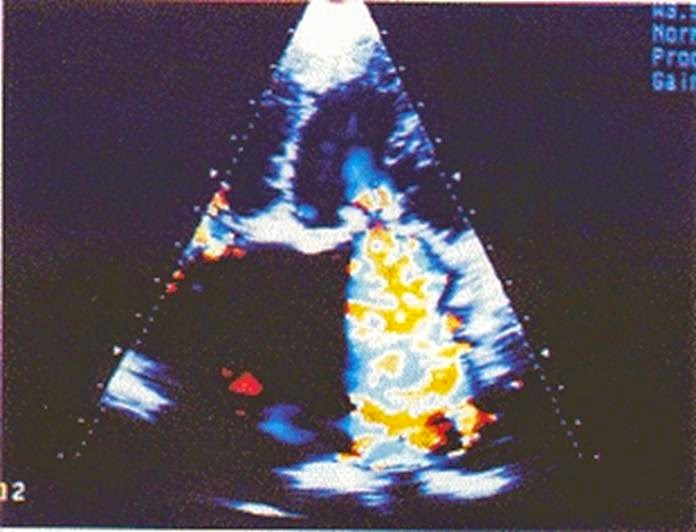

![]() |

| Hở hai lá trong NMCT |